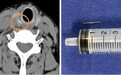

医生从患者右侧甲状腺中,取出了一枚长约1.5厘米的鱼刺。上海市第十人民医院 供图

手术中,医生小心翼翼地探入患者颈部,精细地分离组织,完好地保护其甲状腺、甲状旁腺以及喉返神经,最终成功从患者右侧甲状腺中取出了一枚长约1.5厘米的鱼刺。探查还发现,患者周围的食道黏膜有轻度肿胀,遂对创面作了消毒处理。术后,李阿姨喉咙疼痛明显减轻,经过抗炎治疗,颈部的切口愈合良好。